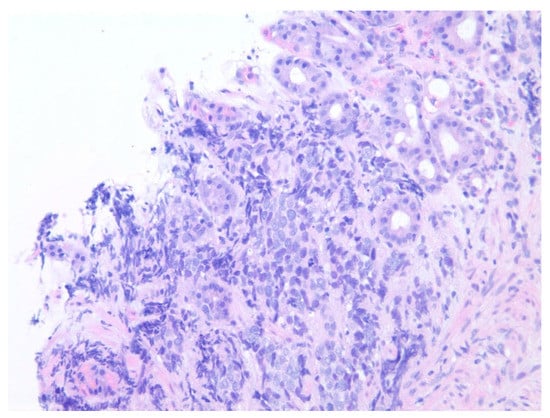

| 2 | M | 84 | Lymphoid | Fundus and cardia | Ulcerated and necrotic mass | Liver, urinary bladder | Diffuse large B-cell lymphoma | None | Death in 2 months after EGD diagnosis of metastasis |

| 5 | M | 76 | Lung | Body | Cratered ulcers | Liver, bone and adrenals | Small cell carcinoma (poorly differentiated neuroendocrine Ca) | None | Death 7 days after EGD diagnosis of metastasis |

| 6 | M | 61 | Lymphoid | Unknown | Clean based ulcer | None | Marginal zone lymphoma | Rituximab, Zanubrutinib, umbrasilib. OCHOP regimen currently | Progressive disease per latest scans despite therapy |